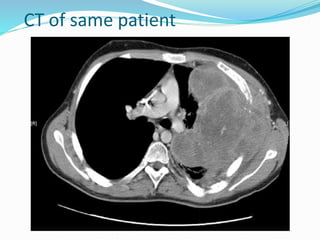

Pleural effusion with complete

right lower lobe collapse

This is a chest x ray taken from a 48y male

Who presented with left sided chest pain

Dry cough and wt loss since 4 month.

Chest x ray showed a left opaque

Thorax with mediastinal shift opposite to

Opacified side,

These findings was suggestive of a massive

Pleural effusion on clinico-radiological

Assessment.

However thoracocentesis revealed dry tap

On ultrasound of the chest disclosed a

solid, smooth marginated mass

occupying the left hemithorax with

multiple well-defined

rounded cystic spaces and focal areas of

calcification. There was no pleural effusion.

Computed tomography (CT) of the thorax showed

a well-defined heterogeneously enhancing mass

measuring 16.6cm x 13.7cm, and occupying almost

the whole of the left hemi thorax. The mass showed

non-enhancing areas with CT values of 40±5 HU

suggesting a cystic degeneration and areas of

calcification. The mass displaced the mediastinum to

the right side with preservation of the fat planes

between the mediastinum and the mass.

Bipopsy confirmed the case as giant primary pulmonary

fibrosarcoma.